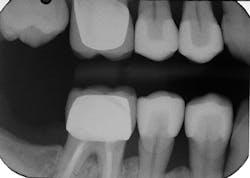

Lastly, the intaglio of the crowns was treated with hydrofluoric acid and silane as described above, and definitive cementation was accomplished using Prime&Bond Elect and Calibra Ceram. Final occlusion and interproximal contacts were checked, and the patient was released after receiving four individual crown restorations all completed in one visit (figures 6 and 7).

Figure 7: Final radiograph of Celtra Duo crowns on teeth Nos. 4, 5, 28, 29 after definitive cementation with Calibra Ceram and Prime&Bond Elect.